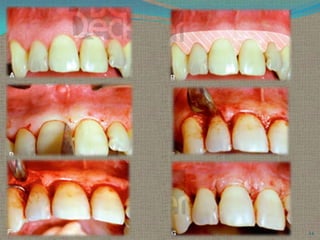

CLINICAL APPEARANCE AFTER SCALING AND CURETTAGE

Immediately after scaling and curettage, the gingiva appears

hemorrhagic and bright red.

After 1 week,

The gingiva appears reduced in height

owing to an apical shift in the position of the gingival

margin. The gingiva is also slightly redder than normal,

but much less so than on previous days.

After 2 weeks

The normal color, consistency, surface texture, and

contour of the gingiva are attained, and the gingival

margin is well adapted to the tooth

Clinical Appearance Of Gingiva